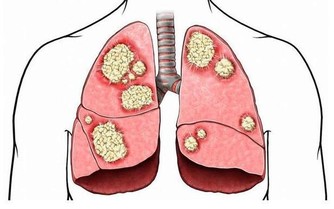

首先是拇指,輕輕按壓及拉扯拇指能舒緩心跳過快、呼吸不順等問題,因為拇指對應到的是心臟及肺部